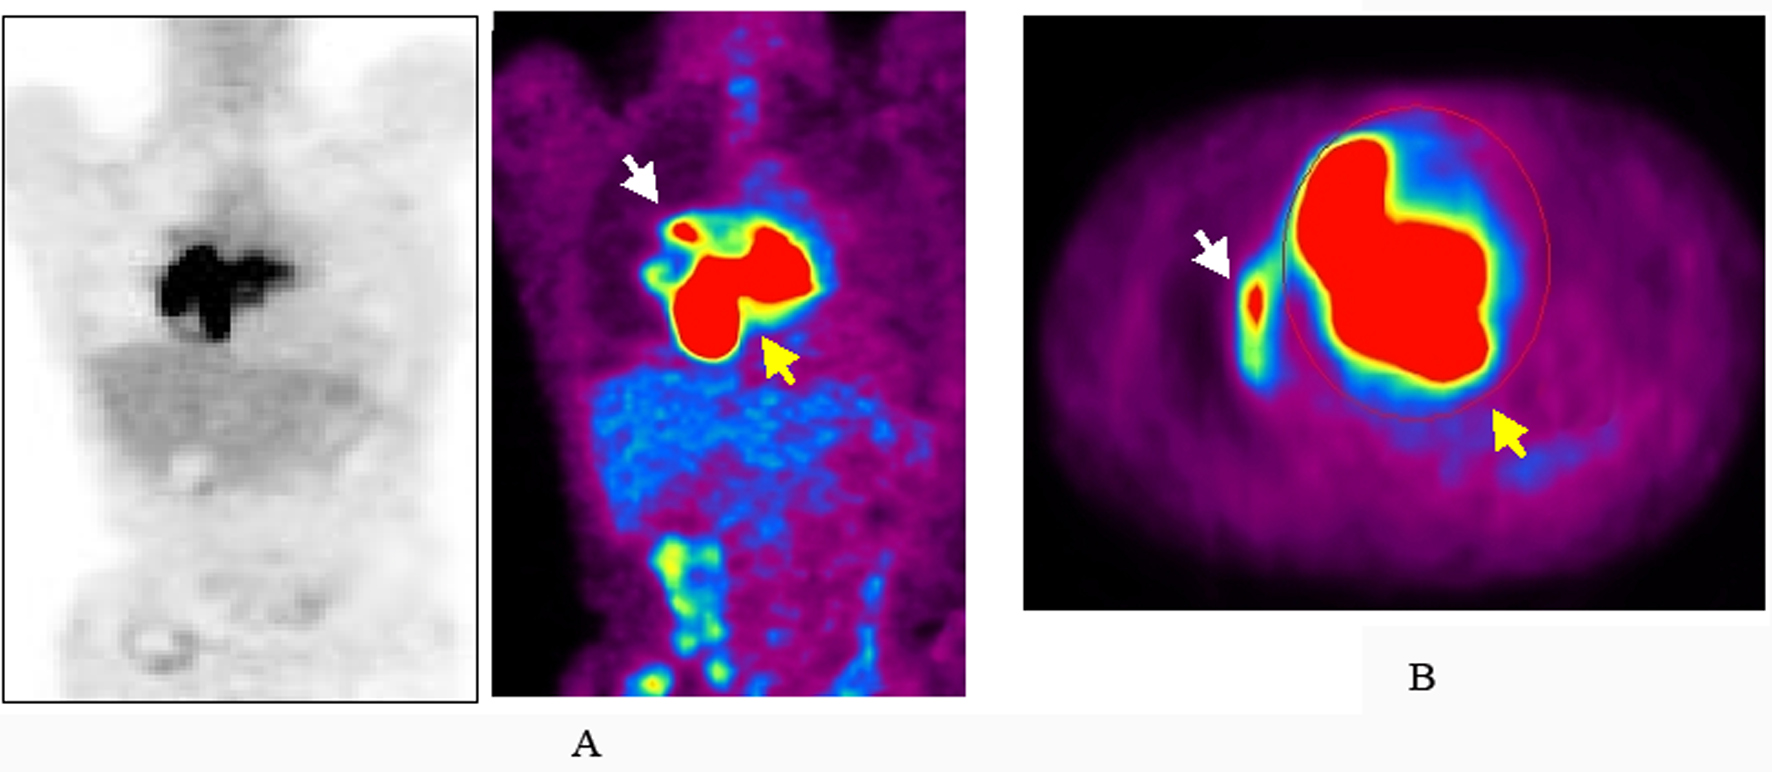

TTE revealed dilatation of the main pulmonary trunk and high systolic pressure gradient across the tricuspid valve of 49 mmHg that is consistent with pulmonary hypertension. There was a thrombus-like mass in the right pulmonary artery and around the left atrium. CT scan similarly revealed a large mass in the proximal portion of right pulmonary artery and around the left atrium, but no abnormal mass detected in the lung and other organs (Fig. 1). However, lung scintigraphy demonstrated little visualization of the right lung on technetium-99m macroaggregated albumin (99mTc-MAA) perfusion scan. Ventilation scan with krypton-81m (81mKr) gas was normal (ventilation-perfusion mismatch). Cardiac catheterization demonstrated mean pulmonary artery pressure of 40 mmHg that indicated pulmonary hypertension. Right pulmonary angiography demonstrated vascularized mass with a fistula from the right pulmonary artery to the left atrium (Fig. 2). To confirm this suspected malignant features and the extent of disease, 18-fluorodeoxyglucose positron emission tomography (FDG-PET) was performed. FDG-PET revealed a large mass at the area of the right pulmonary artery and the bilateral atira with intense uptake of FDG. The maximum standard uptake value (SUVmax) was 25.2. No other undue hypermetabolic lesions were noted elsewhere (Fig. 3).

![]() Click for large image | Figure 3. The image of maximum intensity projection image of 18-fluorodeoxyglucose positron emission tomography (FDG-PET). Increased uptake of FDG at the area of the right pulmonary artery (white arrow) and the bilateral atria (yellow arrow) in coronal (A) and axial (B) views. |

Echocardiography is a fundamental and useful diagnostic tool for pulmonary artery sarcoma. Contrast-enhanced CT scan or magnetic resonance imaging with gadolinium enhancement could be more beneficial for diagnosis of pulmonary artery sarcoma, which could provide the additional information regarding the size, location, attachment, and local extent of the tumor. Recently, FDG-PET has been reported to be useful for evaluation of the local invasion and distant metastasis of malignant cardiac tumors and for monitoring the response to therapy [16-19]. In addition, Ito et al reported FDG-PET can distinguish pulmonary artery sarcoma from venous pulmonary thromboembolism based on the FDG uptake with SUVmax (7.63 ± 2.21 vs. 2.31 ± 0.41) [18]. In our case, the high FDG uptake with SUVmax of 25.2 has highly suspected pulmonary artery sarcoma, but not thromboembolism.